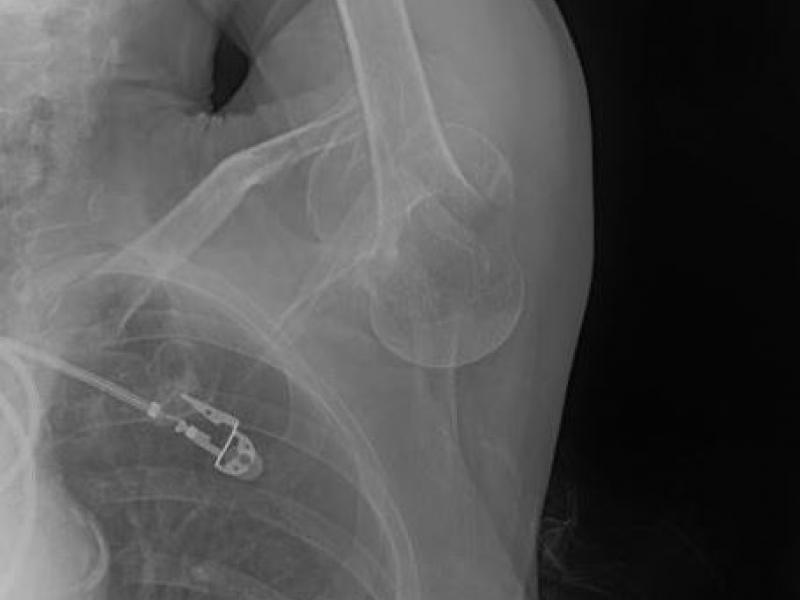

What's the Diagnosis? By Dr. Katie Selman

A 76 yo F presents to the ED w/ L shoulder pain. While